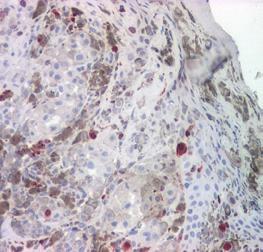

• Examen histopatologic care evidențiază rata mitotică, infiltratul inflamator peritumoral, indice Breslow, nivelul de invazie Clark;

• Imunohistochimie: markeri S100, HMB45 etc.